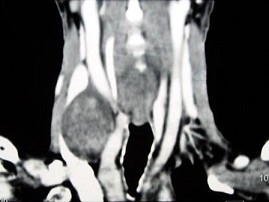

男,70岁,右侧颈部无痛性肿块3个月,CT扫描如图所示,正确的描述或诊断是()

A.右侧颈动脉间隙内见类圆形软组织肿块影,密度欠均匀,边缘光整

B.右侧颈静脉被推压至肿块外后方

C.右侧颈动脉被推压至肿块内后方

D.迷走神经源性肿瘤

E.交感神经源性肿瘤

[多选题] 男,70岁,右侧颈部无痛性肿块3个月,CT扫描如图所示,正确的描述或诊断是()A . 右侧颈动脉间隙内见类圆形软组织肿块影,密度欠均匀,边缘光整B . 右侧颈静脉被推压至肿块外后方C . 右侧颈动脉被推压至肿块内后方D . 迷走神经源性肿瘤E . 交感神经源性肿瘤